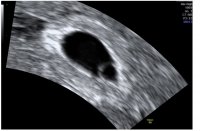

Er vel kun pga sommerferien jeg har ventet så lengeda jeg var innom legen i vinter og sa vi skulle prøve etter mensen i mai, så sa han at han gleda seg på våre vegne, og til jeg skulle på første kontroll rundt uke 8 og se med UL. Meeeeen så kom jo min uke 8 midt i fellesferien

faktisk litt glad for det også, for da får jeg sett mer

hjertet banket og vi fikk til og med et lite hopp. Målte helt riktig til hvor langt jeg var